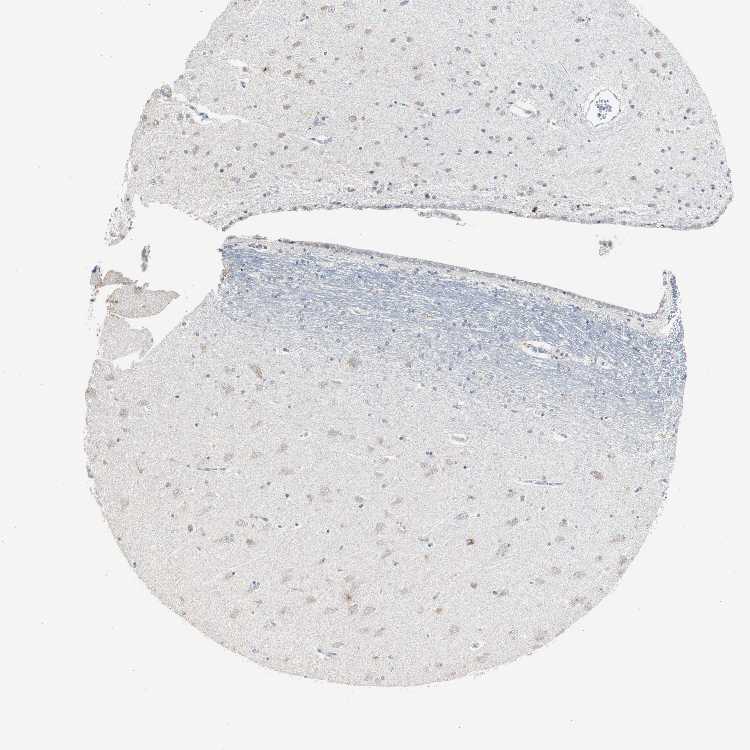

HIPPOCAMPUS - Antibody stainingi

Antibody staining in the annotated cell types in the current human tissue is reported as not detected, low, medium, or high, based on conventional immunohistochemistry profiling in selected tissues. This score is based on the combination of the staining intensity and fraction of stained cells.

Each image is clickable and will lead to virtual microscopy that enables deeper exploration of all samples and also displays staining intensity scores, fraction scores and subcellular localization as well as patient and tissue information for each sample.

Antibody CAB004683

Glial cells Not detected

Neuronal cells Low